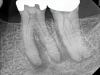

The quality of the initial NSRCT is inversely associated with RETX outcomes, with poorer quality initial treatment tied to more predictable retreatment (Figure 6 through Figure 8).23 Inadequate quality of the initial NSRCT (eg, untreated anatomy, under-instrumentation, ledged and underfilled canals, and overextended obturation) was associated with greater predictability following RETX. However, if clinicians cannot identify and correct the mistakes made in the previous root canal therapy, it becomes more challenging to improve treatment outcomes.23

Fig 6. Identifiable inadequate NSRCT is associated with predictable RETX. Fig 6: Preoperative periapical radiograph showing AP, tooth No. 20. Fig 7. Postoperative periapical radiograph. Fig 8. Six-month follow-up periapical radiograph showing a significant decrease in size of the AP.

Figure 6